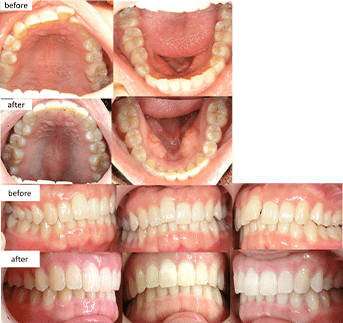

(インビザライン)治療の説明 主訴:叢生 年齢 32歳 抜歯箇所 なし 治療期間 1年1ヶ月 通院回数 10回 ![]()

治療費用 767,800円 治療の内容・詳細 初回と追加アライナーで主訴の叢生を改善、最終左上2番の挺出と嚙み合わせの調整を行い治療を終了いたしました。 治療の副作用(リスク) 保定装置をしっかり装着していないと、後戻りする可能性があります。咬合痛、歯根吸収、歯根露出を生じる可能性があります。